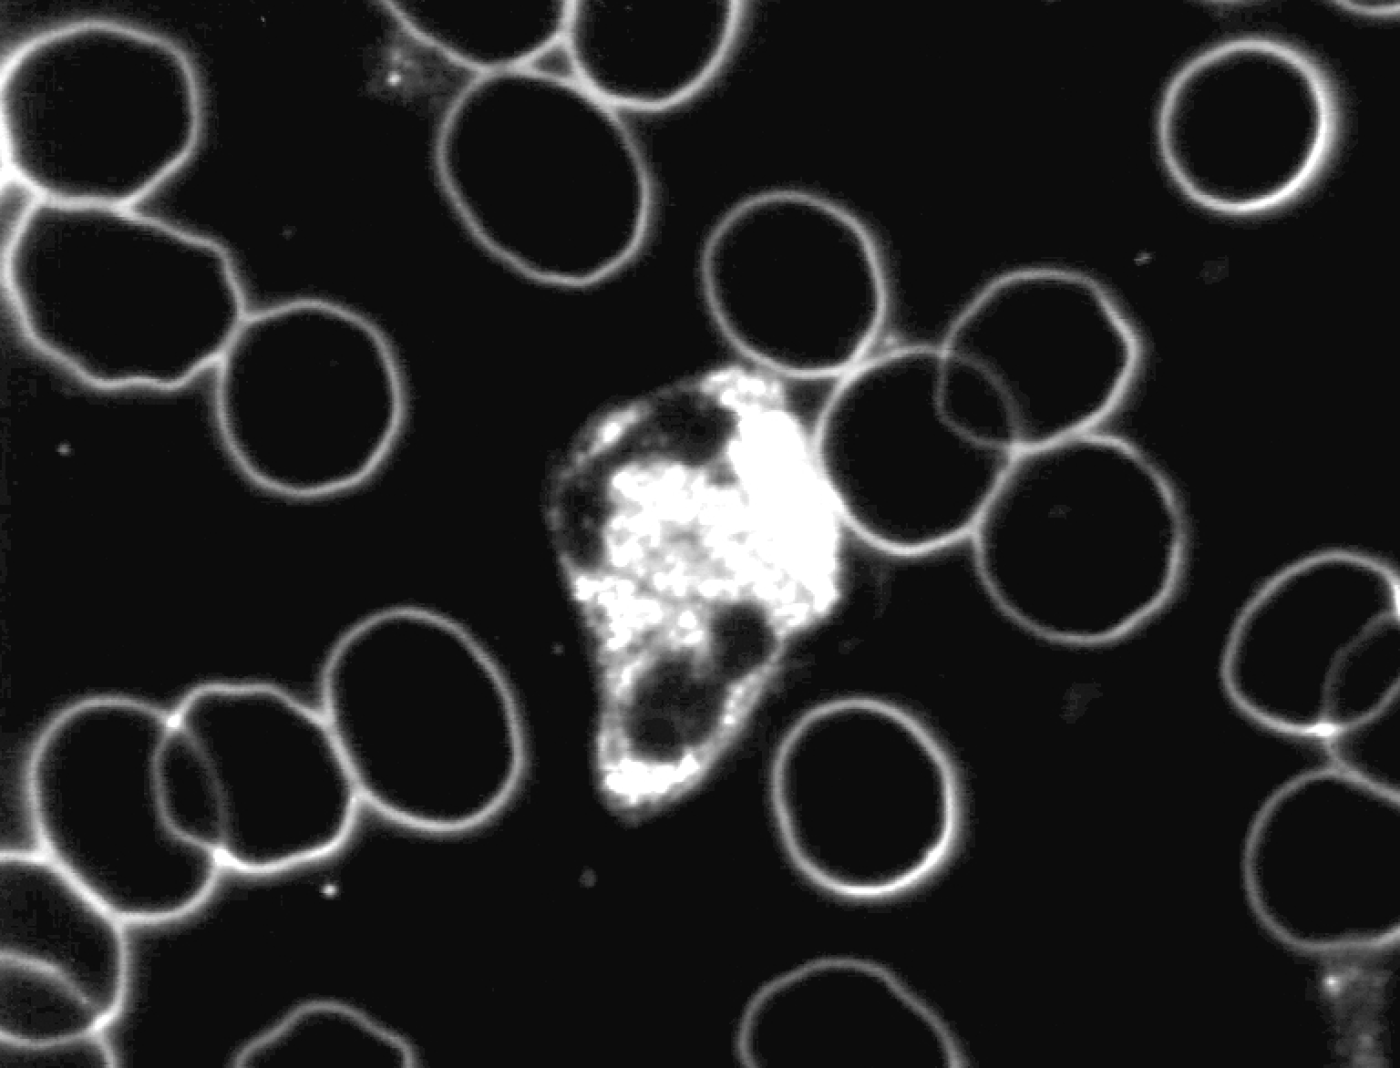

Zie ook onderstaande foto’s met een karakteristiek beeld van vóór en na de neutralisatie met Benzoliet.

Levend bloedbeeld

na neutralisatie met Benzoliet

De veranderingen die werden geconstateerd na neutralisatie van de toegepaste verstorende subtiele energieën door Benzoliet in met name de witte cellen waren:

- toegenomen mobiliteit

- toegenomen en homogeen over de cel verspreide cytoplasmatische activiteit

- verlaten van de bolvorm

- het vormen van pseudopodieën

Hieruit volgt de conclusie dat Benzoliet in staat is de in de proef toegepaste verstorende subtiele energieën te neutraliseren en dat door neutralisatie het afweersysteem beter kan functioneren.